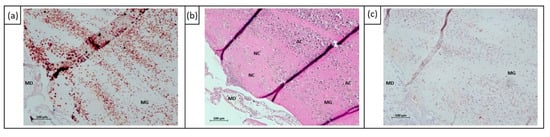

2.2. In Vivo Effects of ECT on Uveal Melanoma Cells Using Chick Embryo Chorioallantoic Membrane (CAM) Assay

4.6. Immunohistochemistry